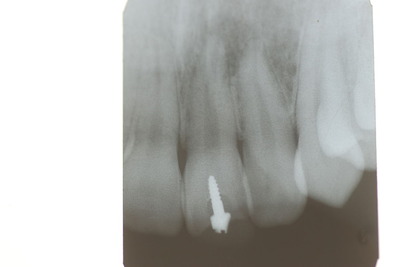

1、先ず一番目は、10才、右の前歯が反対咬合と言って上の歯と下の歯が逆の位置にあり、他の部分があまり咬合していない10才の子供の例でした。噛むと痛みが突然出てしばらく続いていたという症例。

診断を咬合性(歯と歯の噛みあわせ)の急性歯髄炎(神経の炎症)と判断したが、では治療はどうすればいいのかという相談。

レントゲンと話の内容から、食いしばりや歯ぎしりによるものではなく、単純にぶつかる歯が少ないので、その時に前歯のところで何か硬い物などを噛んだために外傷性の痛みが来たのではないかという判断でした。炎症でもないので、奥歯にマウスピースなどを入れて前歯を当たらなくした後に、症状が緩解したら、反対咬合という上下の前歯の関係を簡単な小矯正で変更した方がいいという診断と治療方針の提案で解決しました。

2、67才、女性、主訴は噛みあわせがおかしい。

矯正している。左の上下の6才大臼歯を保険の金属冠から都内の某所でジルコニアという硬いセラミック?冠に変えてからおかしくなっていったそうです。担当の歯科医師は削ったりしてどちらの歯も当たっていないぐらい削っているに違和感が取れないという主訴です。兵庫県の先生からの相談でした。